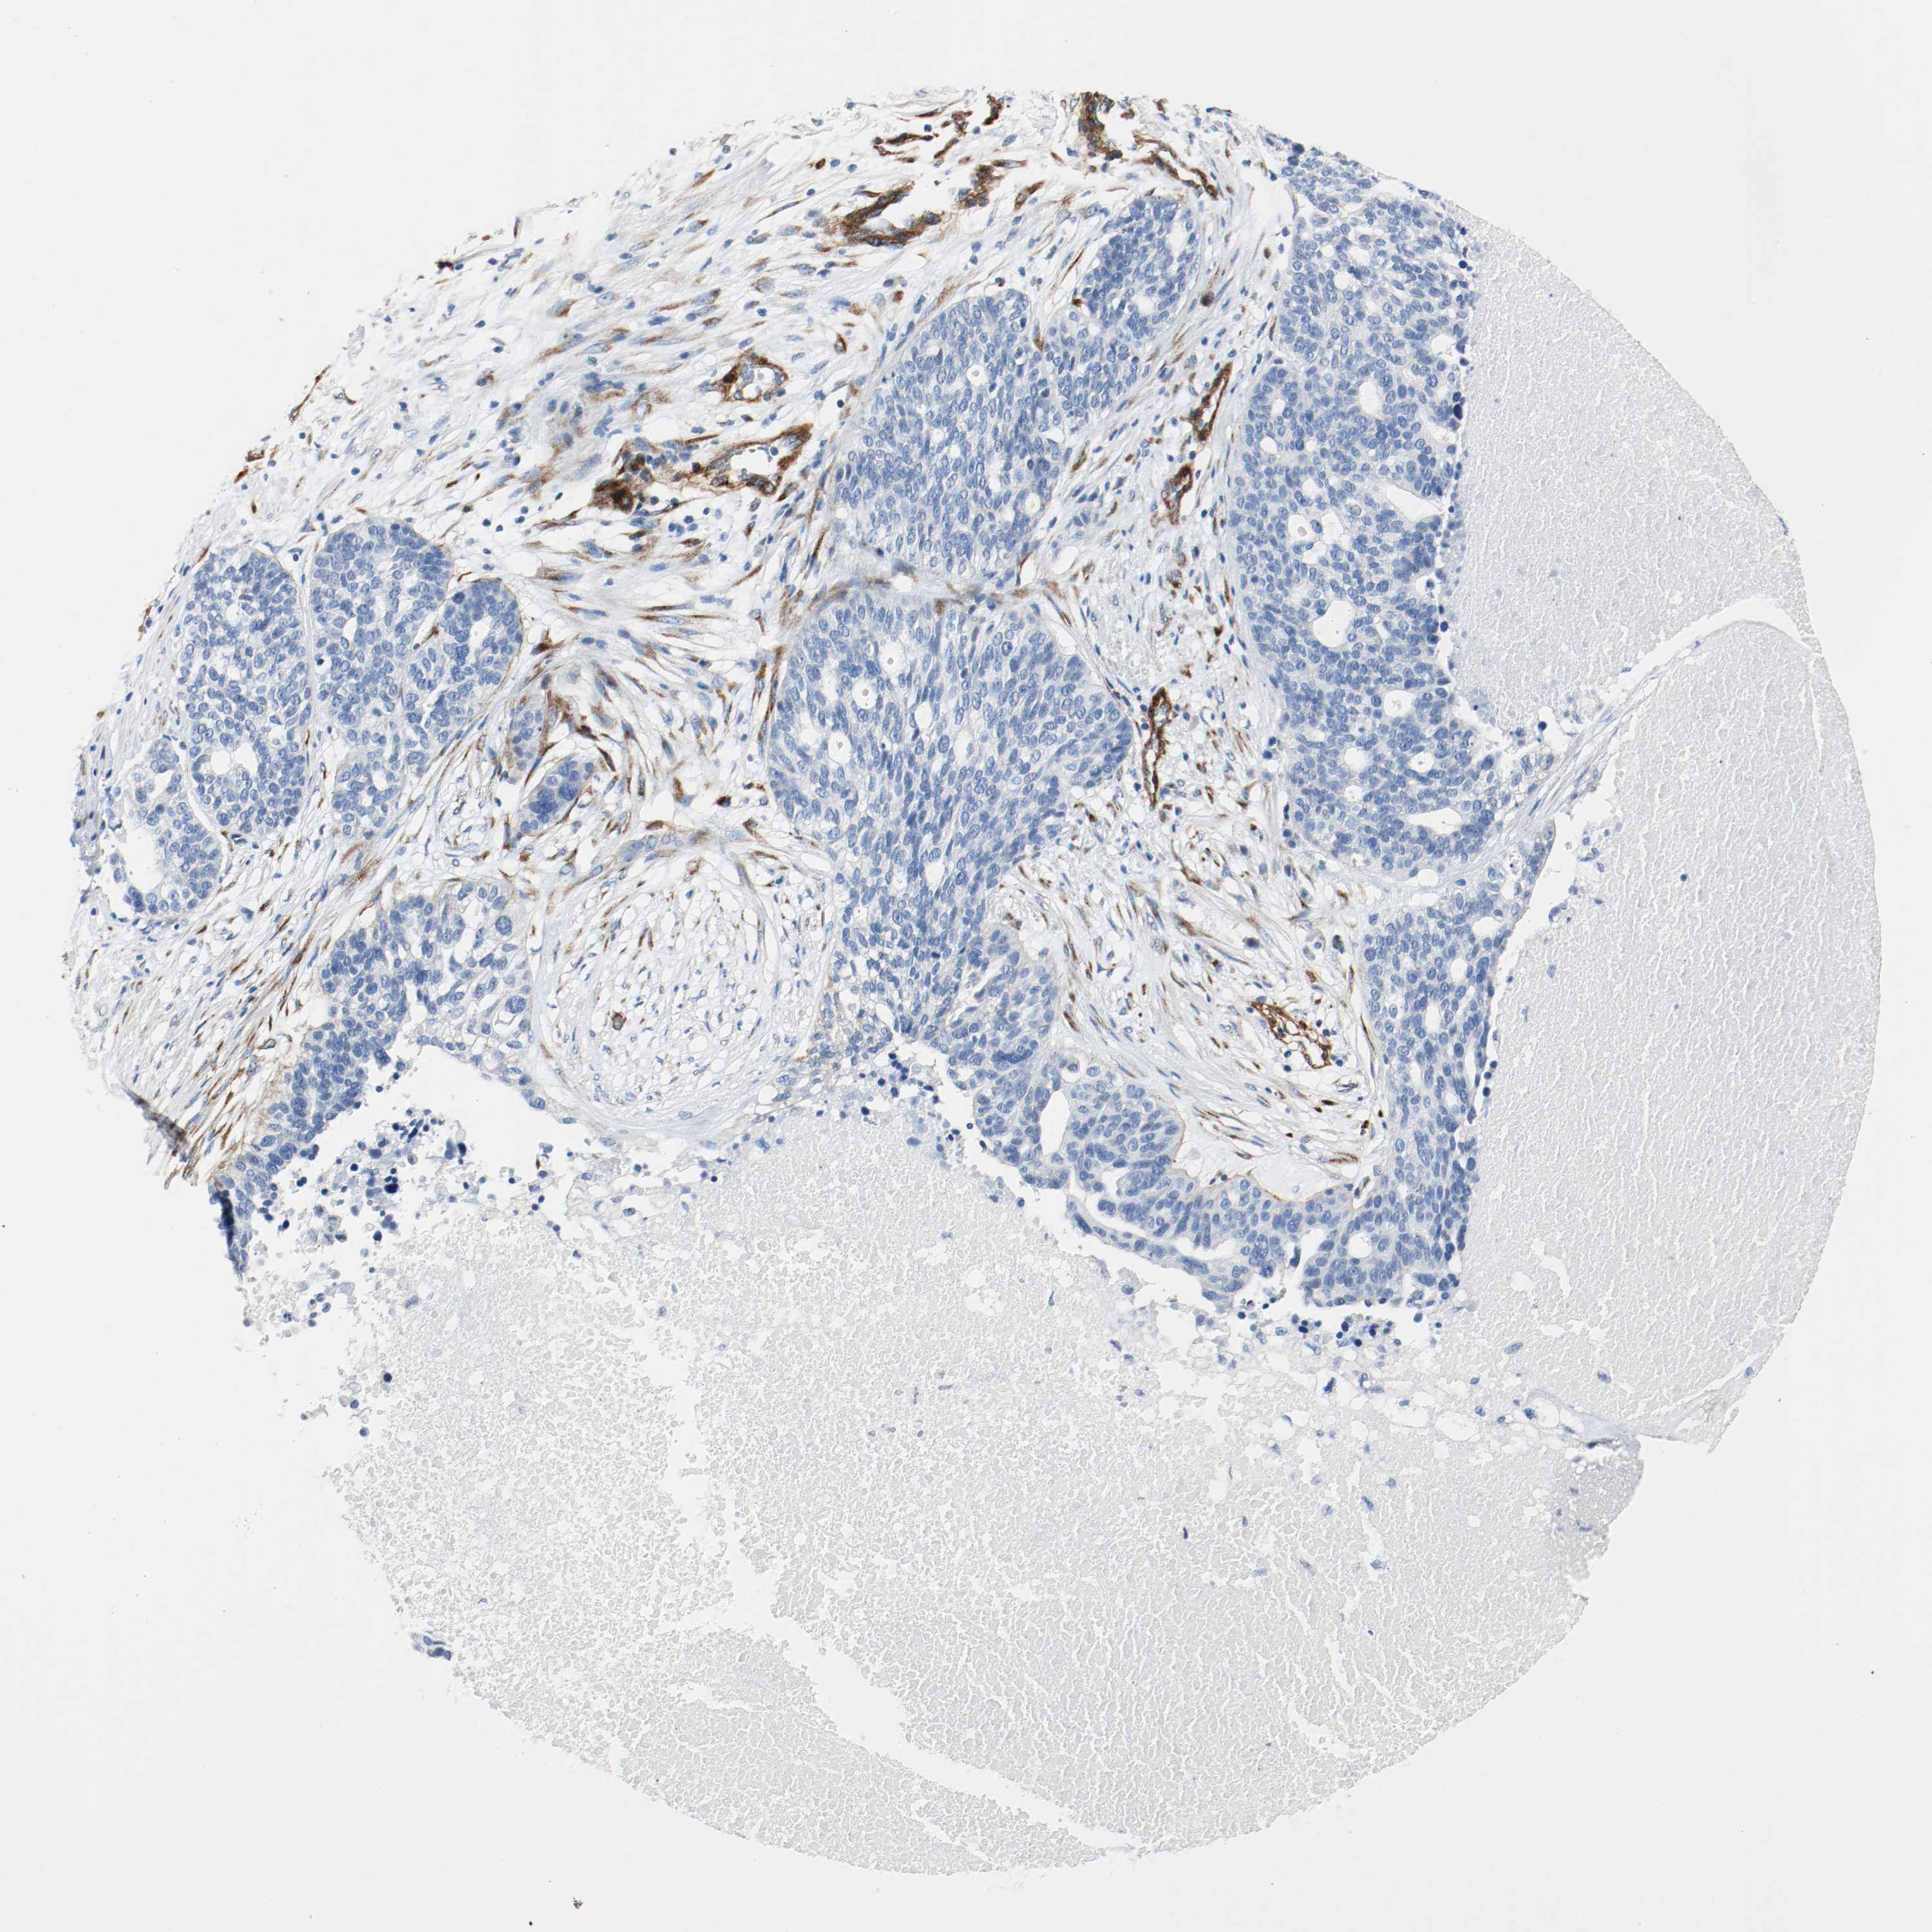

OVARIAN CANCER - Protein expressioni

A mouse-over function shows sample information and annotation data. Click on an image to view it in a full screen mode. Samples can be filtered based on level of antibody staining by selecting one or several of the following categories: high, medium, low and not detected. The assay and annotation is described here.

Note that samples used for immunohistochemistry by the Human Protein Atlas do not correspond to samples in the TCGA dataset.

Antibody stainingi

Antibody staining in the annotated cell types in the current human tissue is reported as not detected, low, medium, or high, based on conventional immunohistochemistry profiling in selected tissues. This score is based on the combination of the staining intensity and fraction of stained cells.

Each image is clickable and will lead to virtual microscopy that enables deeper exploration of all samples and also displays staining intensity scores, fraction scores and subcellular localization as well as patient and tissue information for each sample.

Antibody HPA004056

Antibody HPA004132

Antibody CAB004256

Cystadenocarcinoma, serous, NOS

Carcinoma, endometroid

Carcinoma, NOS

Cystadenocarcinoma, mucinous, NOS